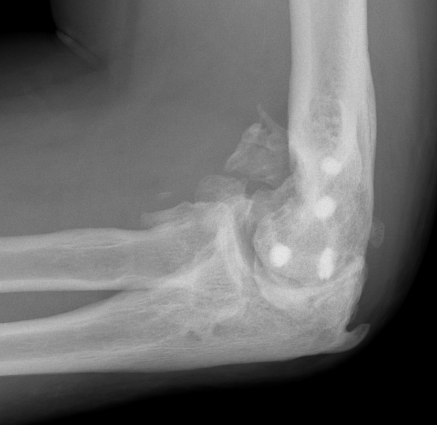

Xray

Mature bone

- smooth well demarcated edges on xray

Complete elbow ankylosis

Shivdasani et al JSES Int 2024

- 107 cases of elbow HO with complete elbow ankylosis undergoing HO resection

- 75% achieved ROM of 100 degrees

- patients maintained 95% of intra-operative ROM

- average extension loss of 20 degrees